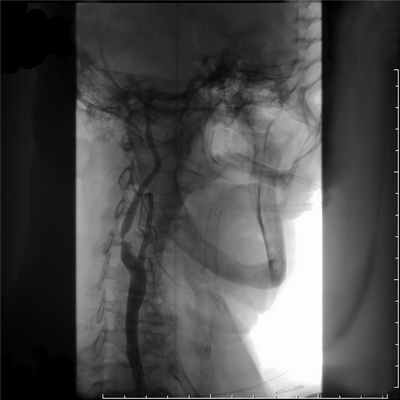

Указанных выше исследований достаточно для постановки диагноза. При решении вопроса об операции используют рентгеноконтрастное исследование. Показания к его проведению тождественны тем, которые используются при хирургическом лечении. Больным, которым не планируется оперативное вмешательство, ангиографическое исследование не проводят. Аортография выполняется по Сельдингеру (через непораженную бедренную или подмышечную артерию) или путем высокой транслюм-бальной пункции. Аортография позволяет оценить состояние дистально-го артериального и коллатериального русла, определить точную локализацию и протяженность окклюзирую-щего процесса. При выполнении аортографии брюшного отдела целесообразно делать снимки с захватом почечных артерий, поскольку почти у 1/3 пациентов с окклюзией терминального отдела аорты имеется артериальная гипертензия, которая может быть обусловлена стенозом почечных артерий. С этой же целью может использоваться МРА или электроннолучевая ангиография.

Большое значение имеет ангиографическое исследование с контрастированием сосудов. Обычно используют поясничную аортографию по методу Дос-Сантоса. Ее проводят следующим образом. Больного укладывают на живот на стол рентгеновского аппарата. Специальную иглу диаметром 1.8—2 мм под местной анестезией вкалывают на уровне I поясничного позвонка, на расстоянии 7—8 см от средней линии и проводят косо вверх. При медленном продвижении иглы удастся ощутить пульсацию аорты. О правильном попадании в просвет аорты свидетельствует появление из иглы пульсирующей струн крови. После этого в аорту вводят контрастное вещество и производят рентгеновские снимки. По аортограмме можно определить локализацию и протяженность окклюзии, составить представление о степени развития коллатерального кровообращения и судить о состоянии магистральных артерий нижних конечностей вплоть до голеней и стоп. В аорте наиболее часто поражается ее бифуркация. Реже верхняя граница закупорки достигает уровня отхождения нижней брыжеечной артерии.

Иногда окклюзнонный процесс распространяется даже до устьев почечных артерий. Это так называемые высокие, или инфраренальные, окклюзии брюшной аорты.